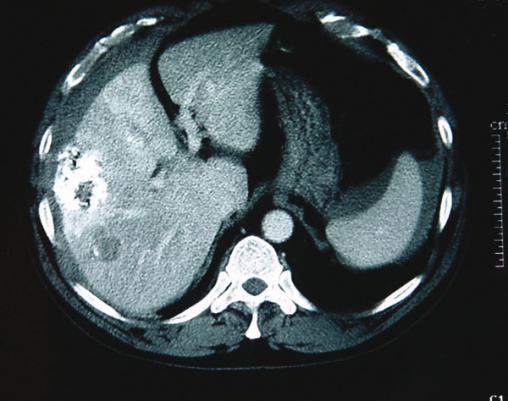

La Revue du Praticien - Jacques Belghiti Tumeur hypervasculaire sous-capsulaire associée à un hémopéritoine. L'artériographie montre la lésion et objective l'hémorragie. Elle permet, de plus, de faire un premier traitement (embolisation artérielle au mieux sélective).